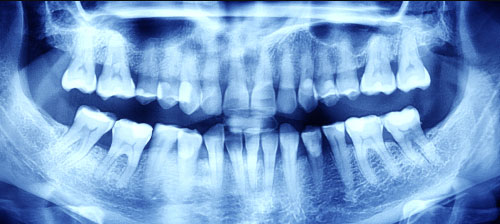

- Occlusal: This is done when your jaw is closed to see how the upper and bottom teeth match up. It can also detect any abnormalities with the floor of the mouth or the palate. This technique shows all of your teeth in one X-ray.

- Panoramic. This type of X-ray involves the machine rotating around your head. Your dentist may use this method to check your wisdom teeth or examine jaw problems.